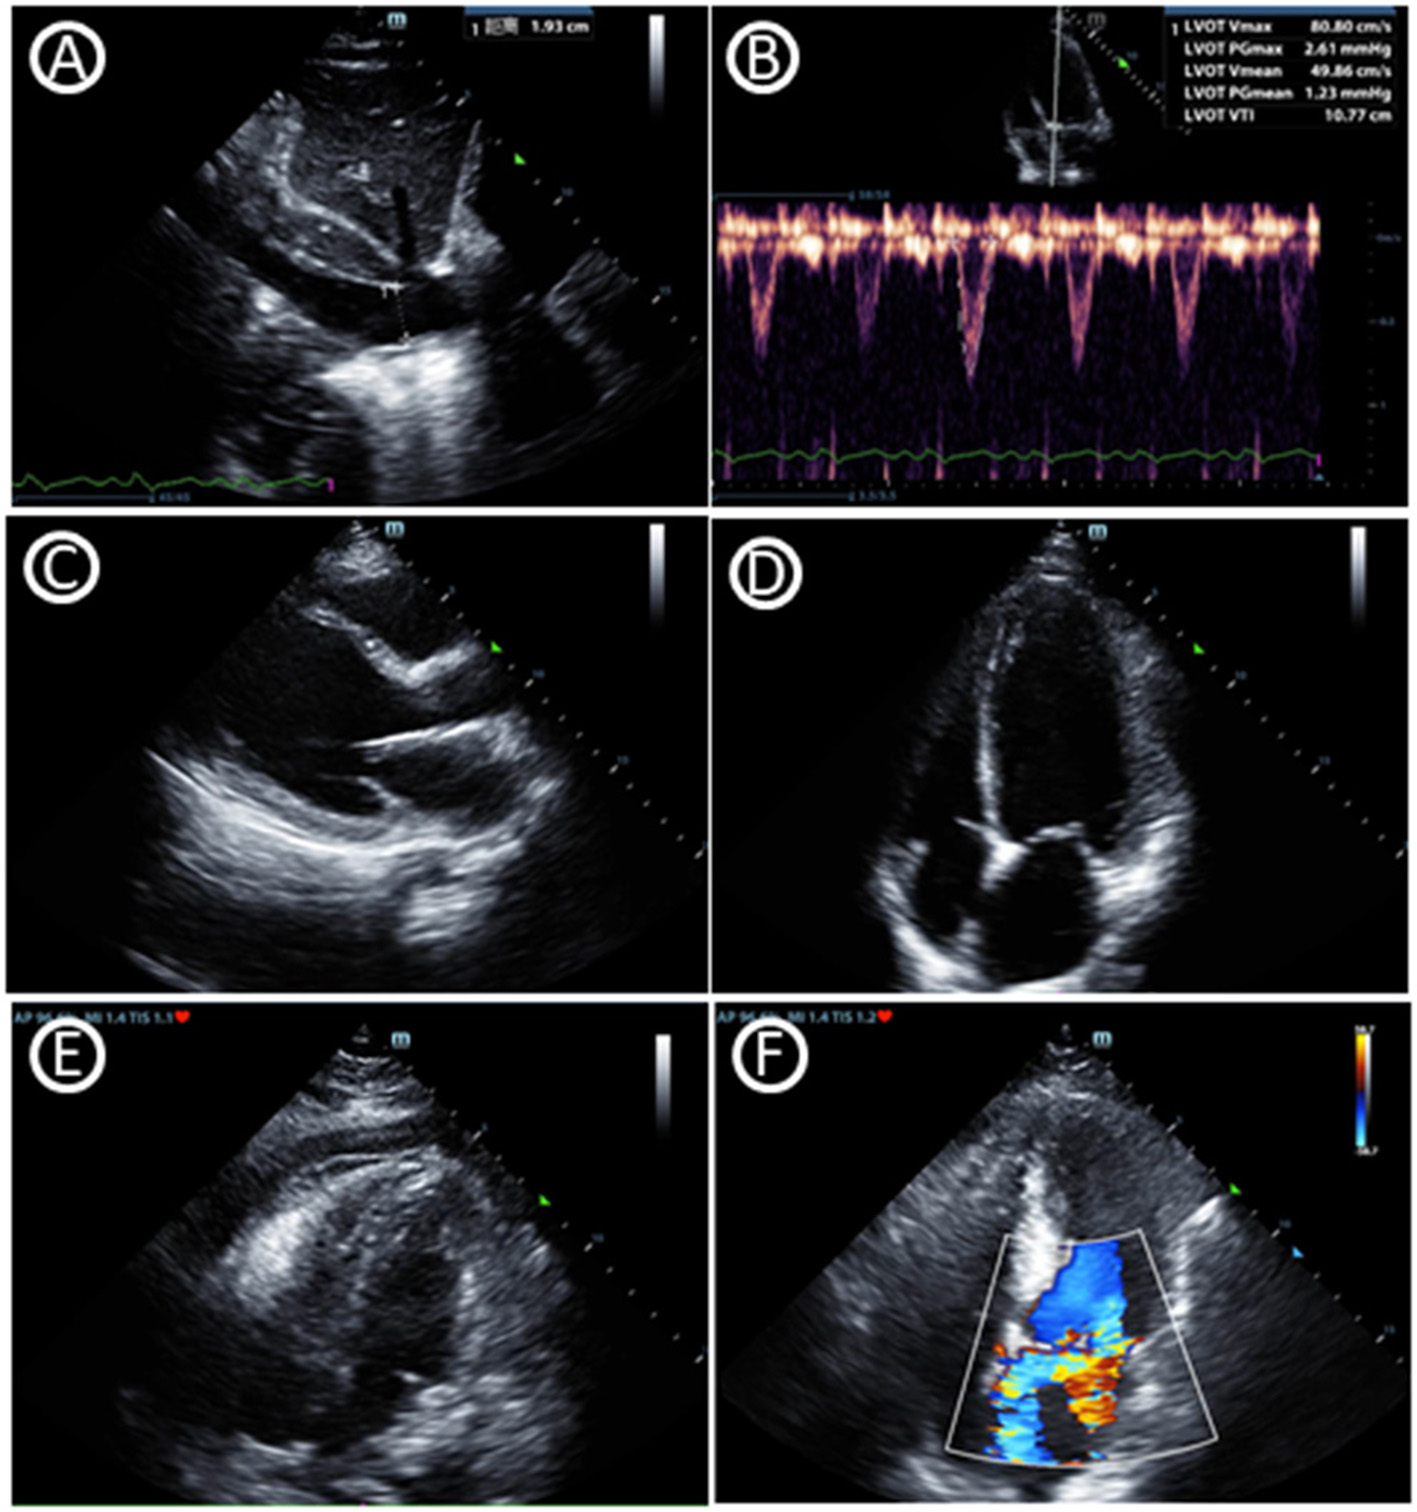

POCUS is not only a diagnostic tool but also helps making clinical decision in real time at the bedside. Critical care echocardiography (CCE) (9), including transthoracic echocardiography (TTE) and transesophageal echocardiography (TEE), facilitates the correct classification of shock (10, 11). 1. Volume Status: A perpetual challenge observed daily in the ICU is estimating volume status and assessing their potential of cardiac output augmentation with the infusion of intravascular volume. The respiratory variation of the inferior vena cava has been widely used to determine volume responsiveness, which should also be interpreted combining the patient's underlying pathophysiological status like the mode of ventilation/respiration, paitient‘s respiratory pattern, cardiac conditions and other factors like increased abdominal pressure (12). Variables based on stroke volume or cardiac output were also combined with other factors to predict flood responsiveness (13). 2. Ventricular Function: Assessment of left ventricular (LV) systolic function (as well as cardiac output), LV diastolic function (left atrial pressure) and right ventricular dysfunction (pulmonary hypertension) are skills required for CCE. LV systolic dysfunction, based on the regions involved, could be divided into regional wall motion abnormality (RWMA) and diffuse hypokinesia. 3. Organic Abnormality: Assessment of valvular stenosis and regurgitation are also skilled by CCE through the application of pulsed wave and continuous wave Doppler. Intensivists with CCE knowledge could assess evidence of pericardial effusion, even cardiac tamponade, which are common reasons of obstructive shock. Left ventricular outflow tract obstruction (LVOTO) can also be easily diagnosed through CCE which is often underestimated in ICU patients (Figure 1).

Figure 1

Critical care echocardiography imaging. (A) Inferior vena cava diameter. (B) Velocity-time integral of left ventricular outflow tract, which can help to gain cardiac output and fluid responsiveness. (C) Parasternal window parasternal long-axis view. (D) Apical window four-chamber view. (E) Pericardial effusion in subcostal window four-chamber view. (F) Mitral regurgitation in apical window four-chamber view.